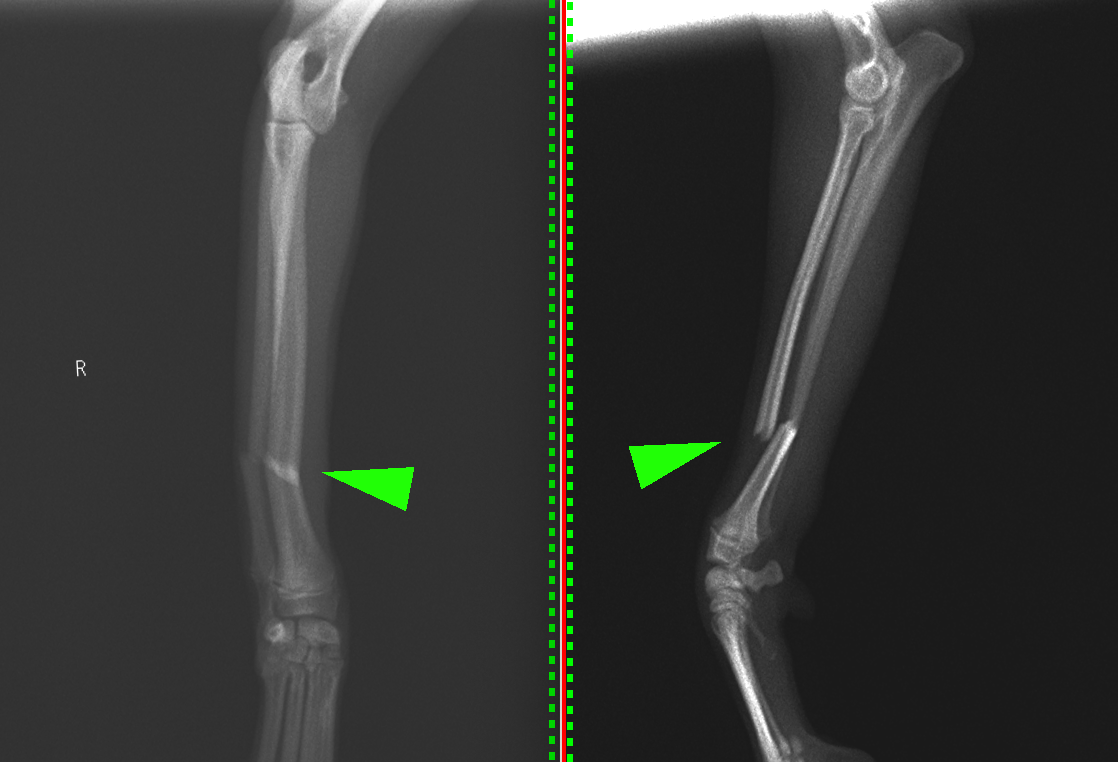

緑矢印が骨折部位です。長い骨の端の方で折れることを、骨幹端骨折といいます。斜めに折れているので、診断名は、左橈尺骨遠位骨幹端斜骨折となります。

少し位置が異なる別の骨折の子のレントゲン画像です。骨の中央付近の骨折なので診断名は橈尺骨骨幹部短斜骨折となります。こちらも直ぐに手術を行いました。

橈骨遠位骨幹端での骨折が確認できました。

完全に折れてしまっている状態です。

正面のプレートを抜去した後のレントゲンです。骨折線がくっついているのがわかります。側面のプレートは残したままでも大丈夫です。